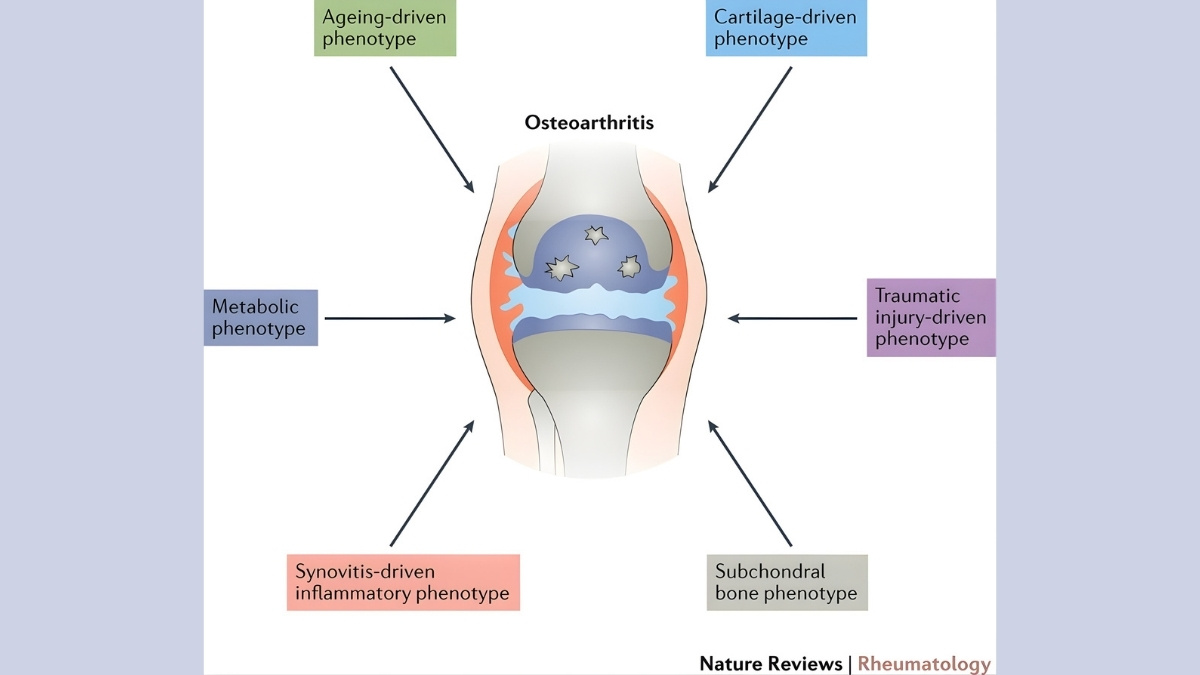

For decades, doctors dismissed osteoarthritis as inevitable wear and tear. But groundbreaking 2024-2025 research from Nature Reviews Rheumatology proves this “joint disease” actually starts in your bloodstream.

Doctors used to think osteoarthritis came from joints wearing out. Like tires on a car. But December 2025 research in Nature Reviews Rheumatology proved them wrong.

A systemic disease affects your whole body, not just one spot. Osteoarthritis is now officially in this category. Your bloodstream carries inflammatory signals to all your joints. This is why understanding OA as a systemic disease matters. It opens up new treatment options you’ve never heard about.